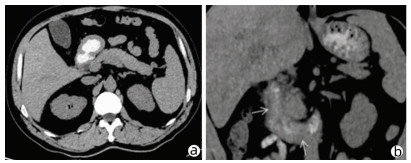

Comorbidity of hepatic cystic echinococcosis with HBV/HCV infection, liver cirrhosis, and hepatocellular carcinoma

Yang MAN, Zhiyi LIN, Zhang MIAO, Lerong YAN, Xiao CHENG, Renyi JING, Rong BAI, Pingwen HUANG, Hongwei ZHANG, Xinyu PENG

2022, 38(3): 601-605. DOI: 10.3969/j.issn.1001-5256.2022.03.020

Abstract(1231) HTML (314) PDF (2056KB)(63)

Abstract:

Objective  To investigate the comorbidity of hepatic cystic echinococcosis with HBV/HCV infection, liver cirrhosis, and hepatocellular carcinoma, and to lay a foundation for further research on the influence of hepatic cystic echinococcosis on HBV/HCV infection, liver cirrhosis, and hepatocellular carcinoma.  Methods  A retrospective analysis was performed for the data of 401 patients with hepatic cystic echinococcosis who were admitted to The First Affiliated Hospital of Shihezi University from 2003 to 2019, and the state of comorbidity of hepatic cystic echinococcosis with HBV/HCV infection, liver cirrhosis, and hepatocellular carcinoma was clarified. The patients with hepatic cystic echinococcosis and chronic HBV/HCV infection were selected as comorbidity group, and the patients with HBV/HCV infection alone were matched as control group. The chi-square test and the Fisher's exact test were used to analyze the state of viral infection and the disease composition of liver cirrhosis and hepatocellular carcinoma.  Results  Of all 401 patients, 38(9.5%) were included in the comorbidity group and 2(0.5%) had liver cirrhosis after HBV/HCV infection, while no patient had hepatocellular carcinoma after HBV/HCV infection. Among the patients with chronic hepatitis B virus infection in the comorbidity group, non-active HBsAg carriers accounted for 81%, HBeAg-positive chronic hepatitis B patients accounted for 9.5%, and HBeAg-negative chronic hepatitis B patients accounted for 9.5%; among the patients with hepatitis B virus infection in the control group, non-active HBsAg carriers accounted for 43%, HBeAg-positive chronic hepatitis B patients accounted for 33%, and HBeAg-negative chronic hepatitis B patients accounted for 19%, with a significant difference between the two groups (P=0.033). There was a significant difference in the HBV RNA clearance rate of the patients with HCV infection between the comorbidity group and the control group (χ2=4.447, P=0.035). In the comorbidity group, the patients with liver cirrhosis accounted for 5.2% and there were no patients with hepatocellular carcinoma, while in the control group, the patients with liver cirrhosis accounted for 18.4% and those with hepatocellular carcinoma accounted for 5.2%; the comorbidity group had significantly lower proportions than the control group (P=0.048).  Conclusion  The proportion of liver cirrhosis patients with hepatic cystic echinococcosis and HBV/HCV infection is lower than that of liver cirrhosis patients with viral hepatitis alone, and there are no cases of hepatocellular carcinoma after HBV/HCV infection. Further multicenter studies are needed to investigate the influence of hepatic cystic echinococcosis on chronic HBV/HCV infection, liver cirrhosis, and hepatocellular carcinoma.